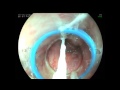

Dr. Deevaguntla Chandrasekar Reddy is a renowned Gastroenterologist and Hepatologist from Hyderabad in Andhra Pradesh with special interest in Liver Diseases treatment and Liver Transplantation. Dr. Reddy has acquired mastery in doing Interventional Endoscopic procedures such as ERCP.

Endoscopic Management of Intra Billary Ruptured Hepatic Hydatid Cyst.